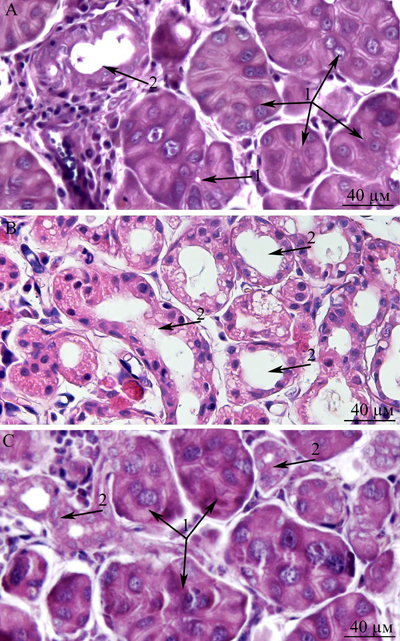

This paper is a continuation of our preliminary study on 3-, 15-, and 24-month-old Wistar rats, where microscopic observation revealed ultrastructural deterioration of the lacrimal gland during aging [27]. Thus, it was interesting to examine age-related ultrastructural alterations of the lacrimal gland in more detail under the influence of the mitochondria-targeted antioxidant SkQ1. Here we shall first dwell on the possibility of quantitation of alterations in the lacrimal-gland ultrastructure directly on the sections during examination under an electron microscope. We must emphasize that these sections were comparable in size with histological sections. We analyzed not only ultrastructural changes in the lacrimal gland but also histological alterations in individual animals (Figure 10a-10c). The histological picture of the lacrimal gland that we observed in the same 24-month-old rats (Figure 10b) is in agreement with the literature data [2-6, 11, 12]. We then compared the results of ultrastructural analysis of lacrimal-gland tissue with the histological data in the same rats (Figure 10b). We saw that the regions of altered acini (according to histological analysis of aging-related changes) are actually regions filled with enlarged intercalary ducts with modified ultrastructure.

We also conducted morphometric analysis of electron-microscopic data from lacrimal-gland preparations (Figure 9). In SkQ1-treated rats, the number of sections of intercalary ducts showing signs of degradation decreased twofold. By contrast, the number of sections of acini showing signs of degradation decreased sevenfold, and the number of unaltered intercalary ducts was an order of magnitude greater in comparison with the untreated animals. The histological picture of the lacrimal gland of SkQ1-treated Wistar rats is in accord with the results of electron microscopy. In the histological samples of lacrimal-gland tissue from SkQ1-treated 24-month-old Wistar rats, the lacrimal gland appears as lobular structures, most of which were unaltered acini. Among them, we saw small intercalary ducts (Figure 10c).

Figure 10: Histological structure of the lacrimal gland. A. A fragment of a lobule from the lacrimal gland of a 3-month-old Wistar rat; B. a fragment of a lobule from the lacrimal gland of a 24-month-old Wistar rat; C. a fragment of a lobule from the lacrimal gland of a 24-month-old Wistar rat that was treated with the antioxidant SkQ1 (starting at age 1.5 months at the dose 250 nmol/ [kg body weight] daily). Arrows “1”: unaltered acini; arrows “2”: intercalary ducts. Staining with hematoxylin and eosin, magnification 400×.